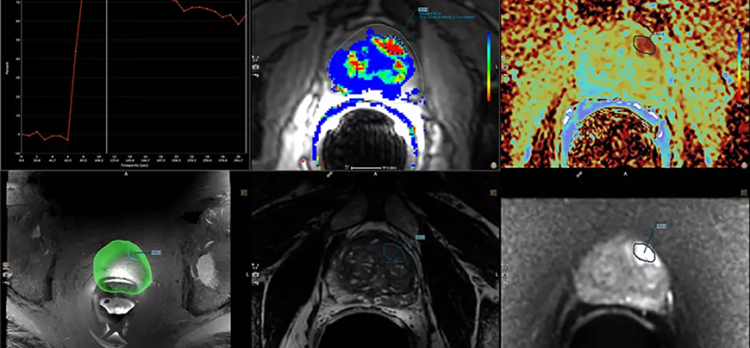

提供一套全面的工具,用于多参数、多供应商 (3) MRI 研究的实时分析、审查和报告。通过将图像直接从 MRI 传输到 DynaCAD 并利用其强大的自动后处理工具,并以定制的悬挂协议显示结果以进行分析和报告,从而提高生产率。

凭借功能强大、易于导航的多供应商 MR 图像分析系统,DynaCAD 可以快速处理和管理大量数据。您可以以即读的自定义悬挂协议打开箱子,所有图像都同步,以便轻松进行多参数审查。

可调节的 3D 分割,用于最佳引导的活检

您可以减少前列腺的手动轮廓:DynaCAD Prostate 基于模型的腺体分割会自动执行腺体的 3D 分割。您可以更改或调整所有三个平面中的分割结果。由此产生的分割报告了总体腺体体积,并为 UroNav MR/US 引导的融合活检程序奠定了基础。

用户生成的 ROI 可以显示在前列腺的 3D 模型以及研究中的多个图像序列上。